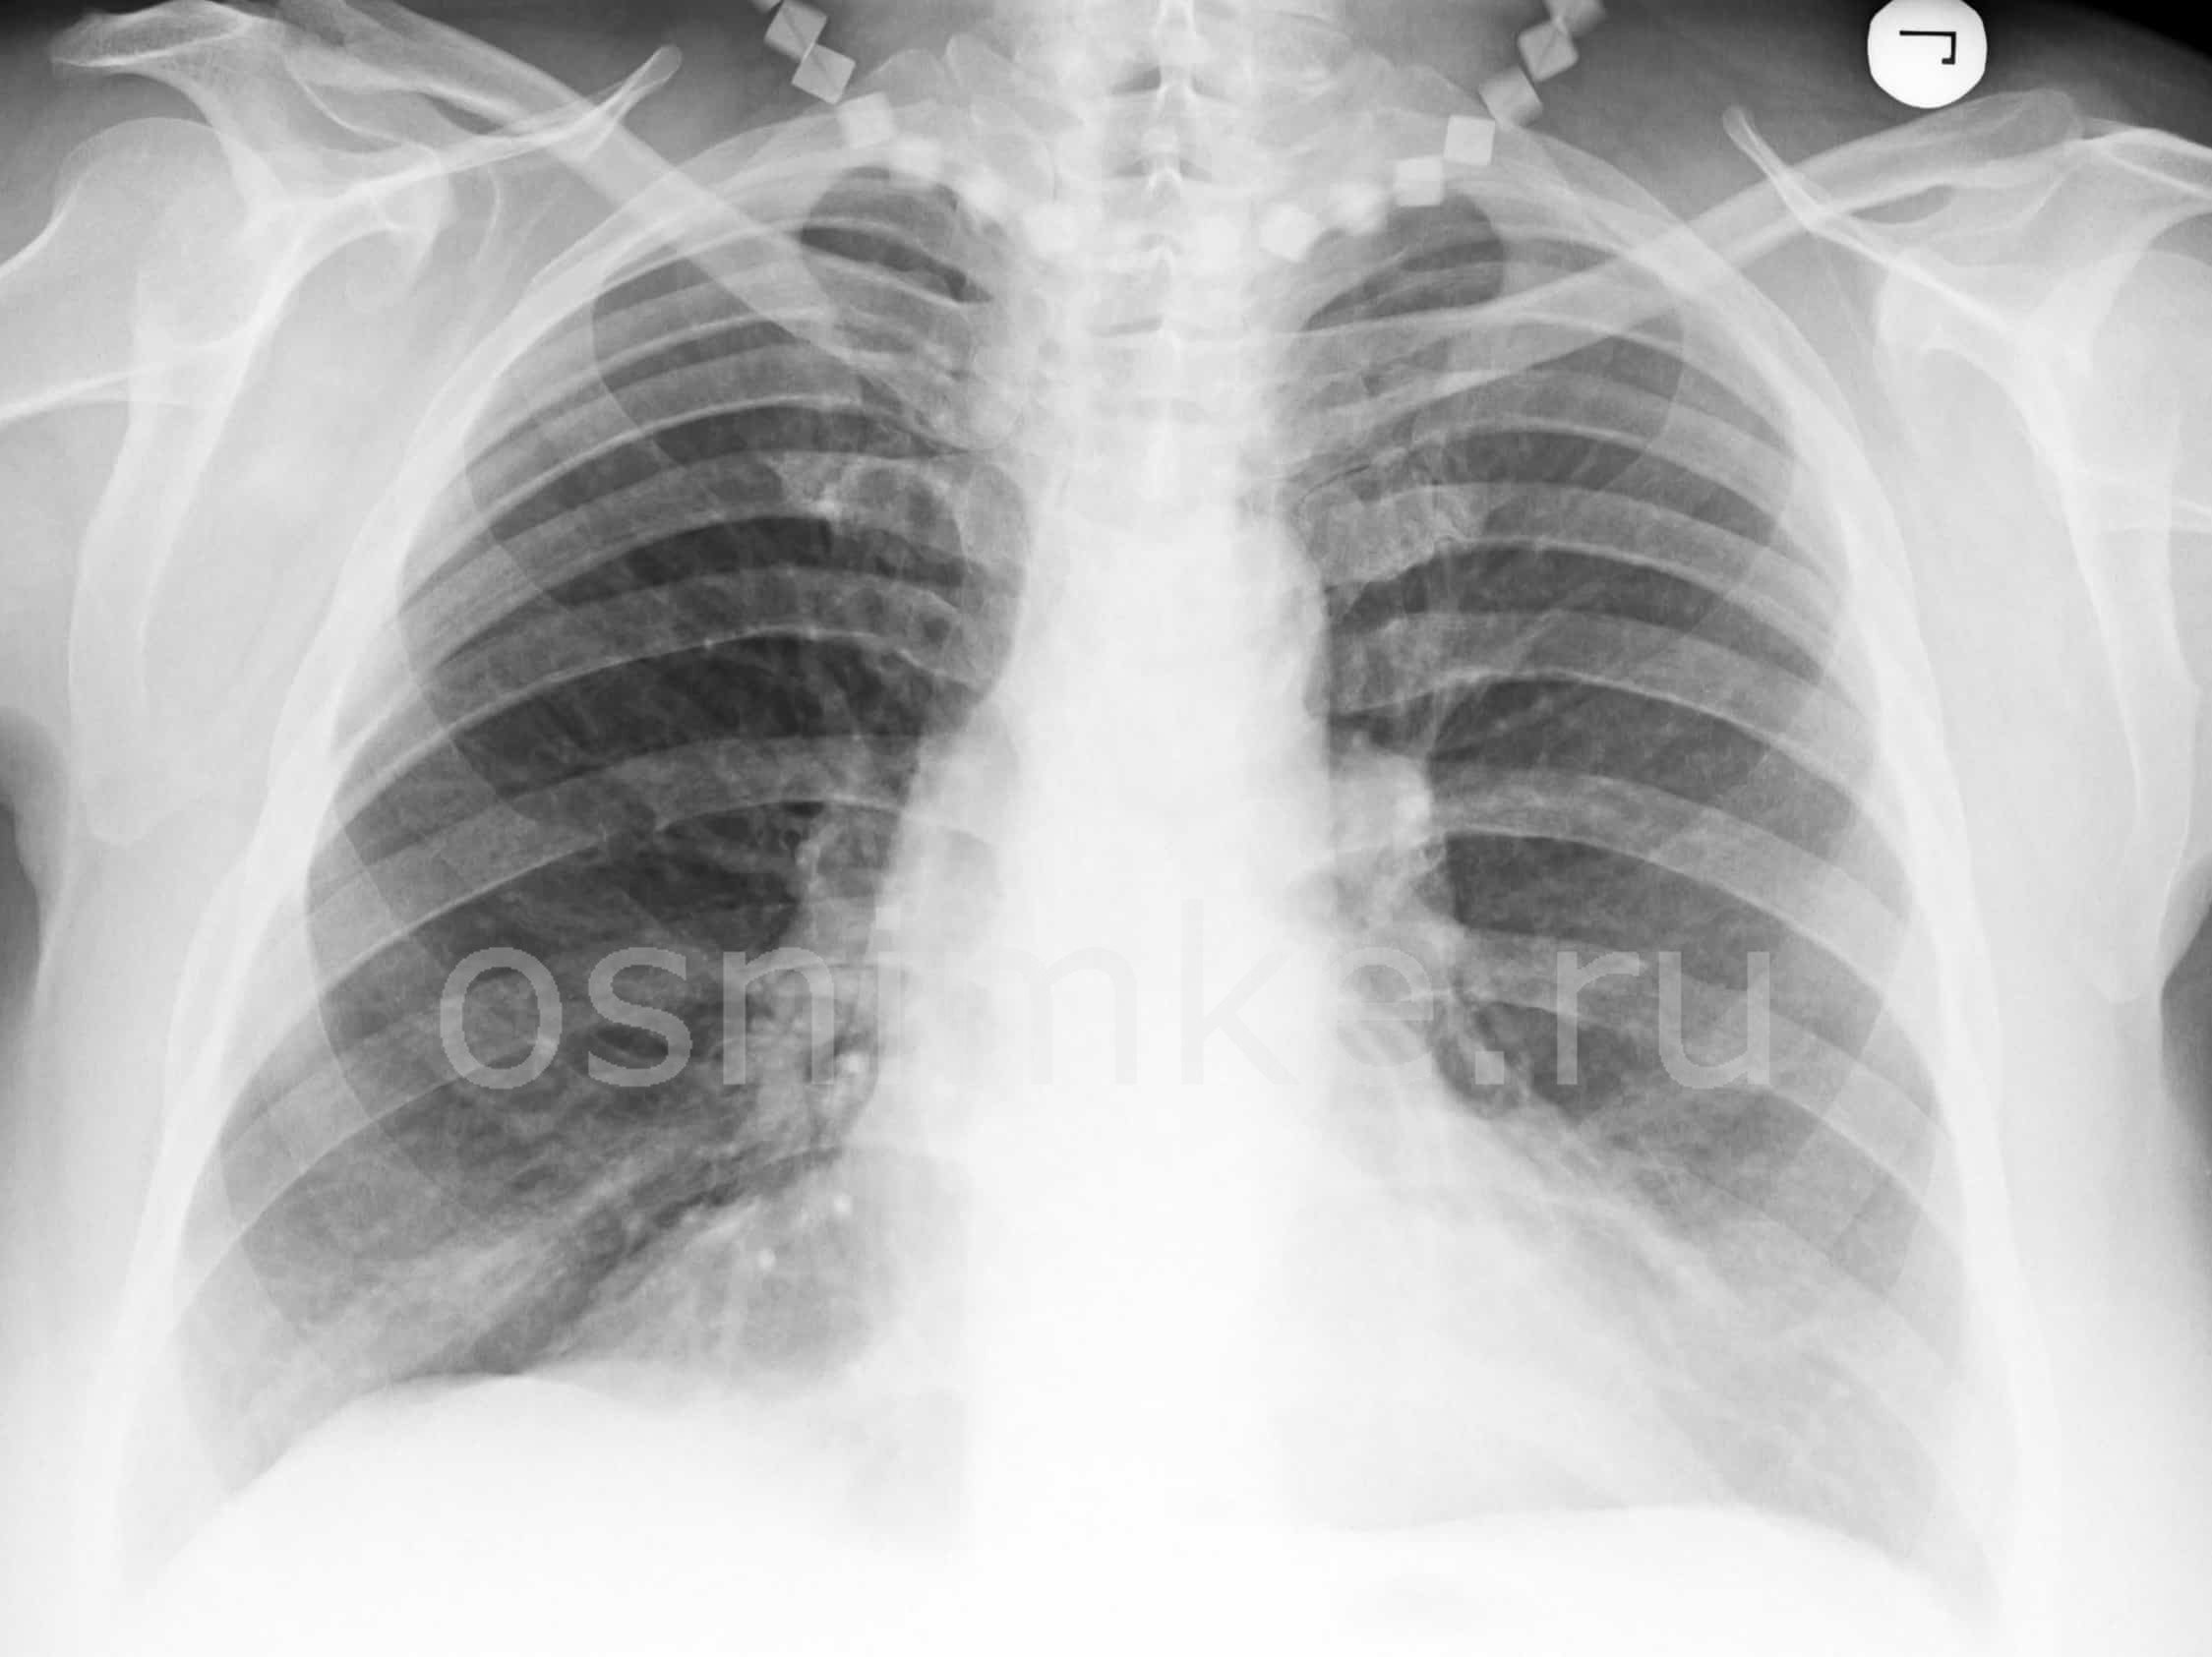

Рентген снимок атипичной пневмонии

Атипичная пневмония — собирательный термин, включающий инфекционно-воспалительные поражения тканей лёгких. Причинами являются нехарактерные возбудители — микоплазма, хламидия, легионелла, вирусы. Воспаление лёгких протекает с повышением температуры, одышкой, общим недомоганием.

Как выглядит пневмония на снимке

Диагностировать патологический процесс можно при помощи рентгена. Так, для микоплазменной формы характерна неоднородная инфильтрация лёгочной ткани, она может определяться слабо или быть среднеинтенсивной.

При легионеллезной, на снимке видно уплотнения (инфильтраты) округлой формы, локализующиеся на поверхности одной доли лёгкого. В ряде случаев наблюдается слияние инфильтратов.

У 25% пациентов одновременно с пневмонией определяется плеврит, с незначительным скоплением секрета в плевральной полости.

Правосторонняя бронхо- пневмония